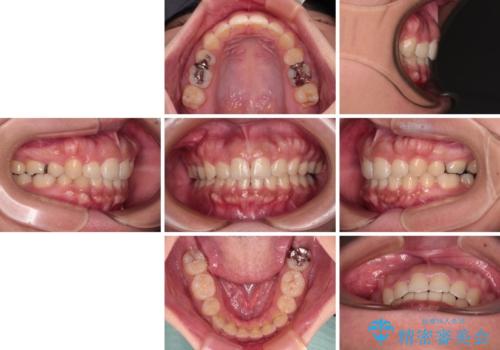

急速拡大とワイヤー抜歯矯正で唇を閉じやすく

デコボコと口元の突出感が認められたため、上下左右の第1小臼歯4本を抜歯してのワイヤー矯正を行うこととしました。

上顎歯列の横幅が狭く、下顎大臼歯の歯軸が舌側に倒れていたため、急速拡大装置により上顎骨を側方に拡大し、咬み合わせを改善することとしました。

上顎歯列幅を拡大したことで、デコボコを容易に解消することができるようになったため、抜歯により得られたスペースを口元の突出感改善に利用することができました。